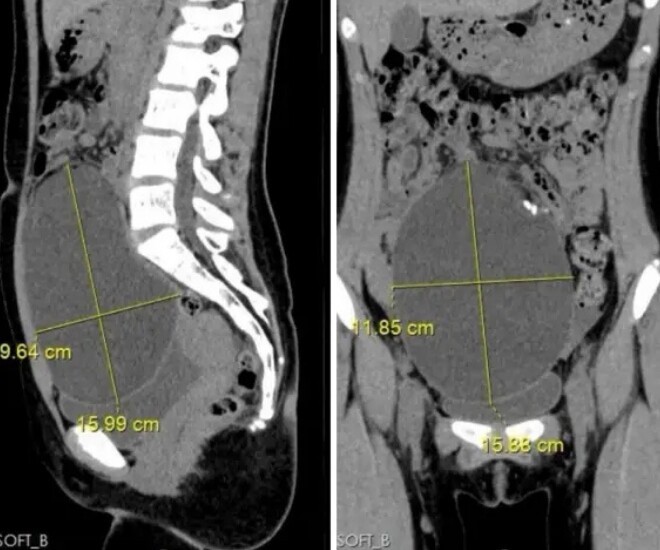

Kết quả chụp CT phát hiện vật thể lạ trong bụng bé gái 12 tuổi.

Kết quả siêu âm khiến bác sĩ bất ngờ còn gia đình thì sợ hãi vì lo lắng, khi phát hiện trong ổ bụng của bé có một khối u lớn. Sau khi chụp CT và thăm khám chuyên sâu, bác sĩ xác định khối u có kích thước lên tới khoảng 16x12x10cm, nghi là u quái buồng trứng.